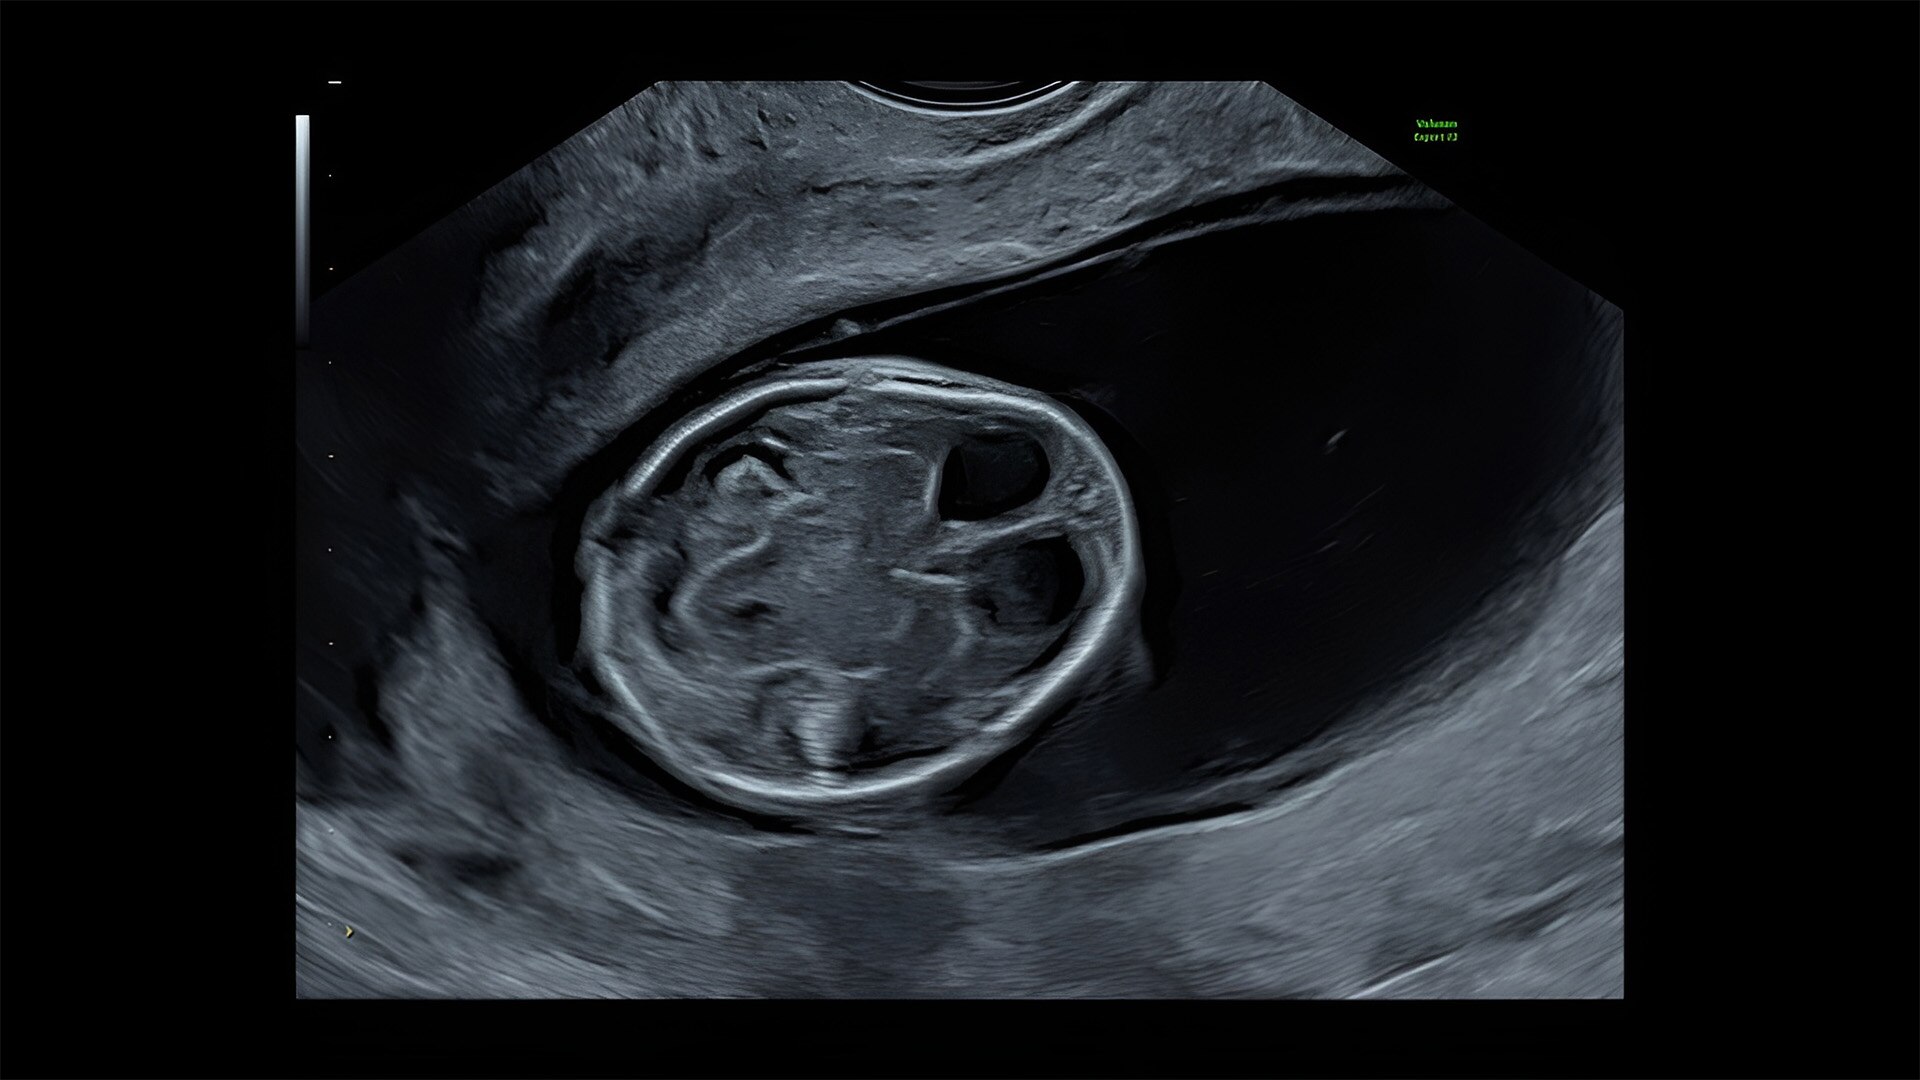

Detect the undetectable

Discover complicated anomalies and pathologies with the Voluson Expert 22 to provide answers sooner for better decision making.

Complex cases come with enough uncertainty. That's why the Voluson Expert 22 is specifically designed for in-depth assessment of complicated anatomy — with pioneering first trimester, fetal cardiac, gynecological, and other pivotal technologies that focus on early detection and intervention.